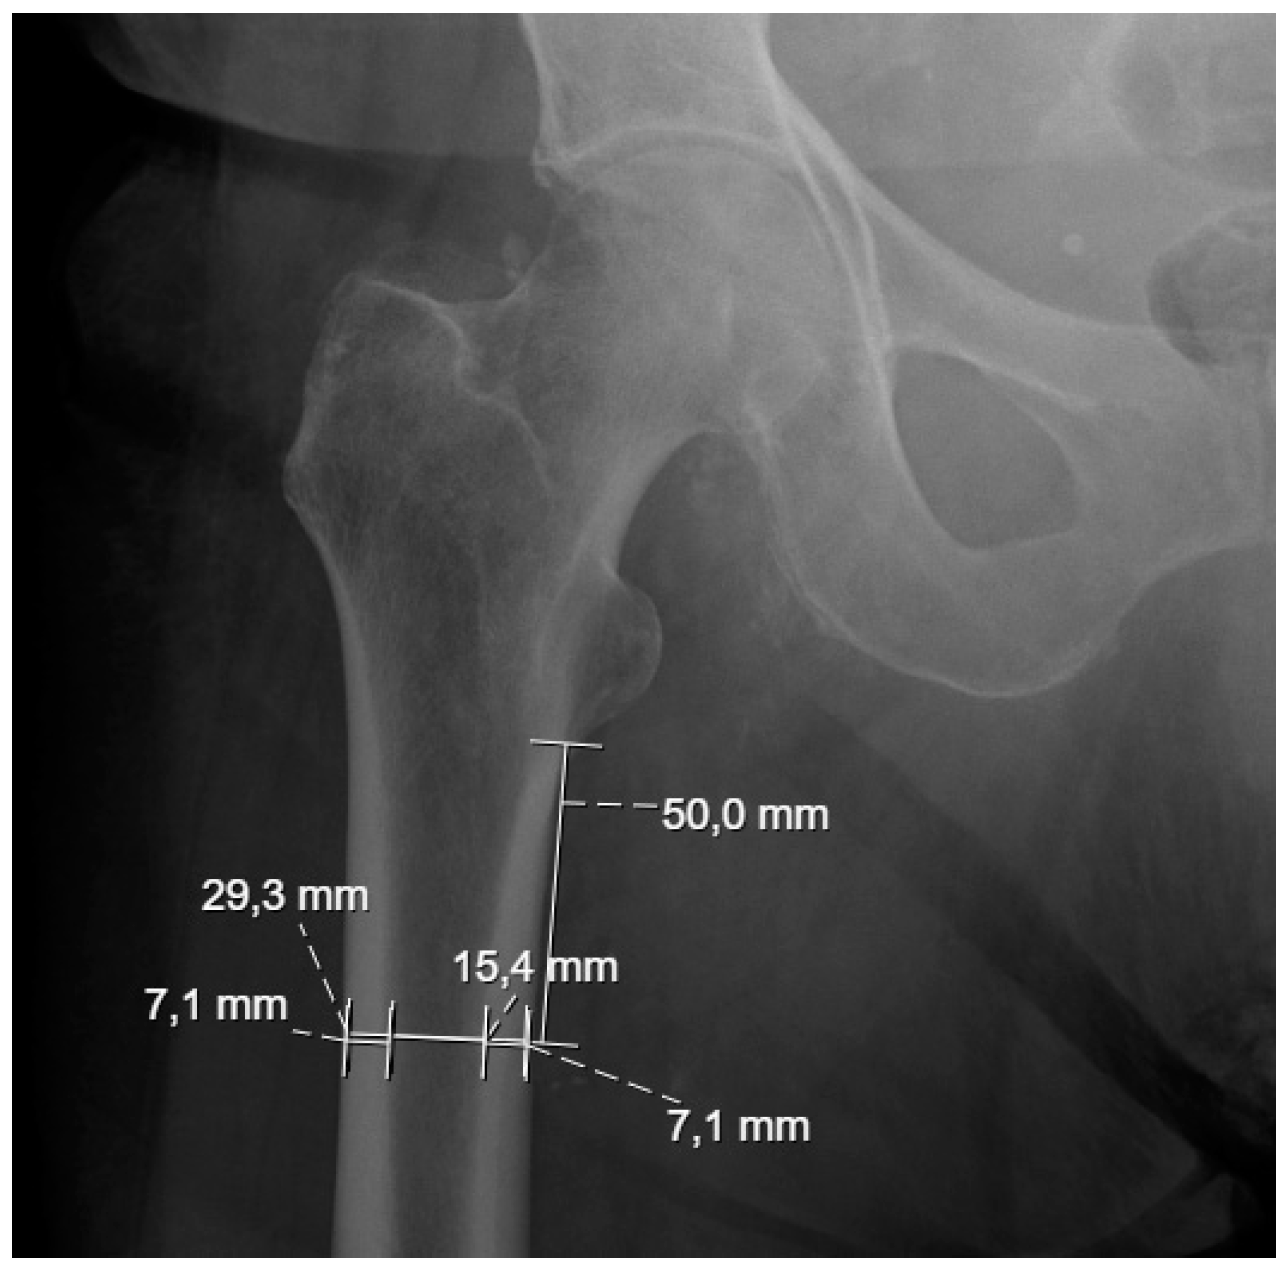

Complex real-life problems can often be represented by mathematical models that can be solved using numerical methods, like the finite element method. In this work, two-dimensional models mimicking femoral metastatic lesions were created by using ANSYS® software version 2024 R2 to evaluate, through thermal and thermomechanical analyses, the effects of different materials in the previously mentioned palliative treatments of bone metastases. The geometries were built using the average dimensions of the subtrochanteric region of 20 non-tumoral patients from the Centro Hospitalar Universitário de Santo António ULSSA (Porto), obtained from conventional pelvic radiographs, as shown in Figure 1.

To build the numerical models, the patients were divided by gender, as shown in Table 1. Each gender was segmented by age group, splitting those under and over 70 years old, which allowed for the creation of four distinct geometries from the average measurements resulting from the external bone diameter (DE) and internal bone diameter (DI). This ensured a more comprehensive representation of the physical and anatomical characteristics associated with gender and age. The data in Table 1 were obtained from conventional pelvic radiographs of 20 non-tumor patients (10 female and 10 male) at the Centro Hospitalar do Porto. At 50 mm from the lesser trochanter, measurements were taken of the internal and external cortical thickness, the diameter of the cancellous bone (corresponding to 15.4 mm in Figure 1), and the total femur diameter (29.3 mm in Figure 1). Each measured value presented in Table 1 was obtained from different measurements along the cancellous and cortical bone of each subject and represents the mean.

Figure 1. Measurements used in numerical models.